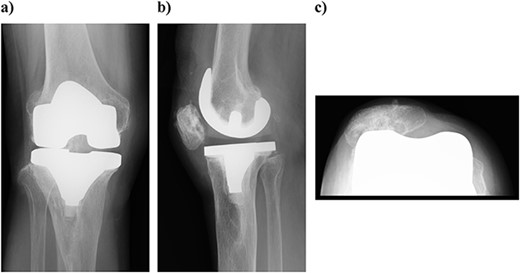

At 3 years postoperatively, the patient could walk independently. Her extension and flexion were − 5° and 120°, respectively, her KS score was 83 points, and her KS-F score was 90 points. Radiography showed a slight valgus position, with some lateral subluxation of the patella, but the patient reported no problems with her activities of daily living (Fig. 5).

Outcome at 3 years after surgery on plain radiography: (a) standing front and (b) side. The patella is laterally subluxated in a slight valgus position.